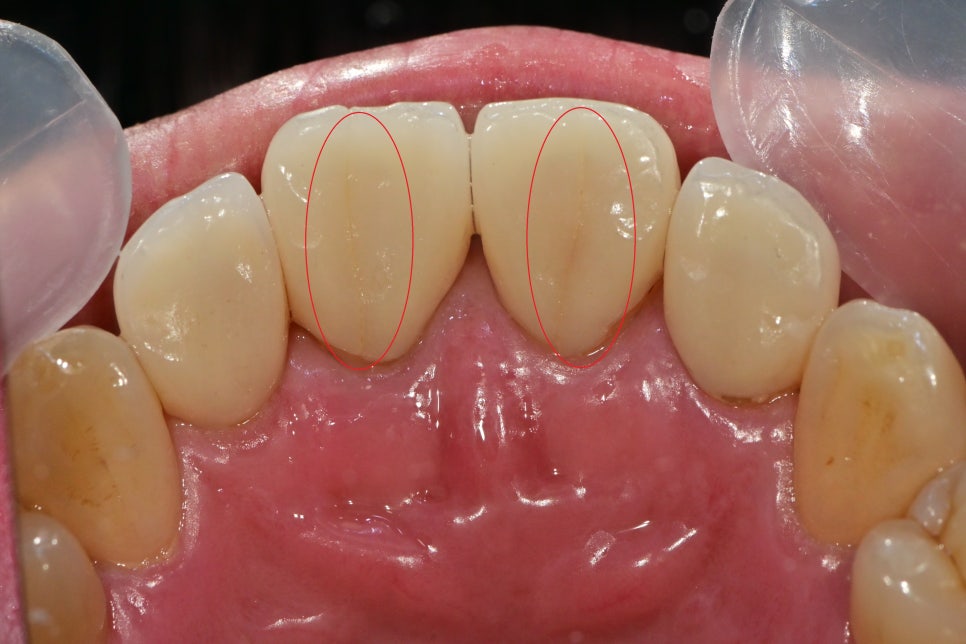

안쪽에서 보면 명확하게 보입니다.

앞니 4개를 하셨는데 그중에 2개가 금이 생겨있었습니다.

빨간색 동그라미는 치아의 색상을 카테고리화 시킨 것인데

shade guide란것을 이용하여 최대한

주변 치아와 맞는 색을 찾으려 노력을 해봤습니다.

미백에서도 쓰여지고, 심미적인 치료를 할 때는 자주 이용하는 도구입니다.